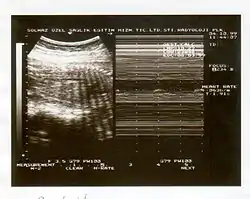

- Determinación de la actividad o reactividad cardíaca fetal, también conocida como una prueba de reactividad fetal, en el que la aceleración de la frecuencia cardíaca fetal se comparan, en el tiempo, con los movimientos fetales a ver si correlacionan. --> Este criterio se ve en el trazado de monitoría fetal. (2 aceleraciones en 20 minutos)